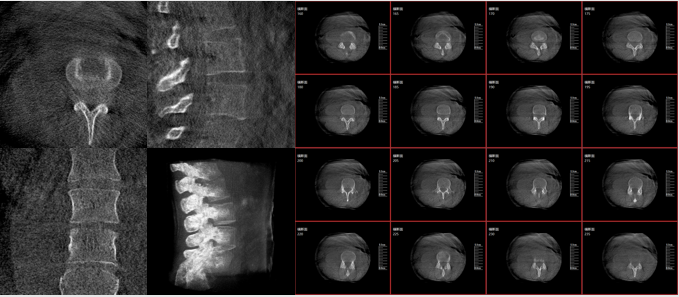

而三维影像的MPR图像组可以通过不同平面的切分,使成像区内更丰富的信息得以呈现。尤其是二维影像无法涉及的横断面,提供了另一个空间维度的信息量。

术中三维C臂影像